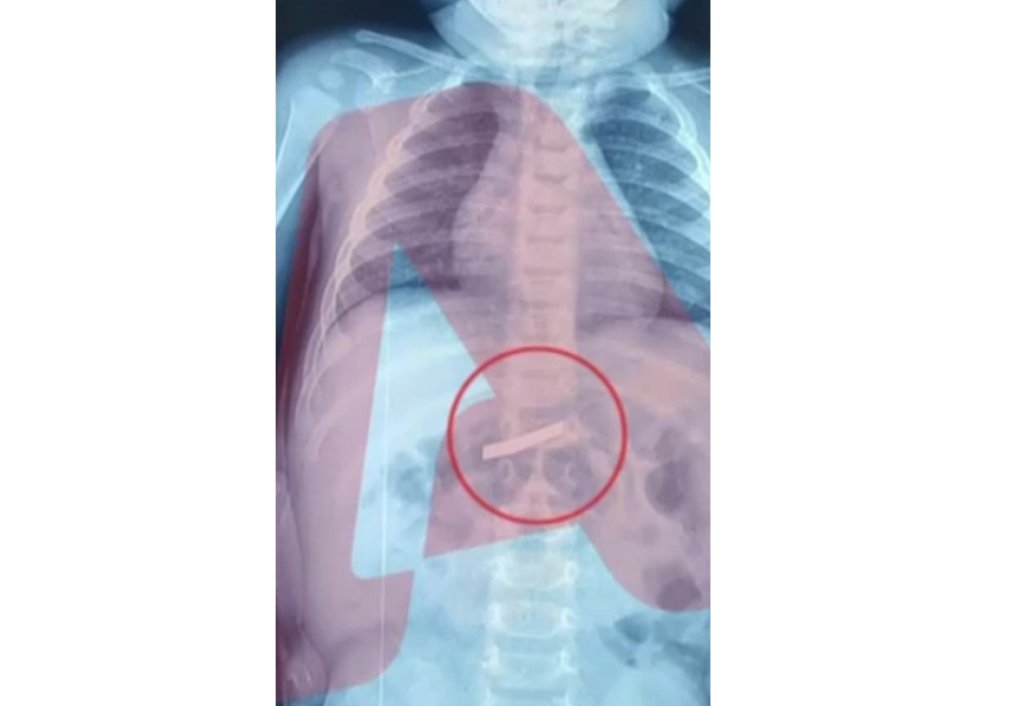

Ένας τρίχρονος μεταφέρθηκε εσπευσμένα στο νοσοκομείο Παίδων της Αθήνας καθώς είχε καταπιεί ξυράφι.

Το παιδί μεταφέρθηκε στο νοσοκομείο το πρωί της Τετάρτης (18/3) με τους γονείς να ενημερώνουν πως είχε καταπιεί ξυράφι.

Έγινε άμεσα ακτινογραφία προκειμένου να εντοπιστεί το ακριβές σημείο στο οποίο ήταν το αιχμηρό αντικείμενο, σύμφωνα με τον Alpha.

Ο 3χρονος χειρουργήθηκε και πλέον έχει διαφύγει τον κίνδυνο.